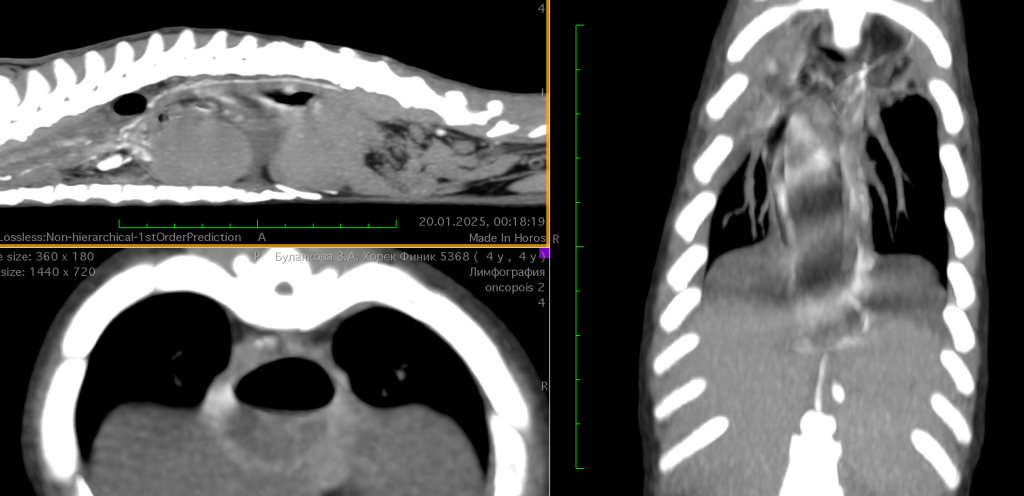

Для уточнения диагноза была проведена непрямая КТ-лимфография путем введения 2 мл йодсодержащего контрастного вещества («Юнигексол») в мякиш правой тазовой конечности. В ходе исследования были выявлены значительное расширение пищевода, гидроторакс и выраженное расширение лимфатических сосудов дистального отдела пищевода вблизи кардии с признаками утечки лимфы в плевральную полость (рис. 2; видео 5). Данных, свидетельствующих о наличии неоплазии, получено не было.

Пациенту была выполнена непрямая КТ-лимфография, при проведении которой обнаружили выраженную дилатацию лимфатических сосудов каудальной части пищевода с признаками утечки контраста в грудную полость диффузно в дистальной части, перед кардиальным сфинктером. Пищевод был значительно расширен, имел S-образный изгиб и занимал 1/3 объема грудной полости. Объективных причин для хилоторакса обнаружено не было, предположительно, хилоторакс сформировался ввиду значительного расширения пищевода, возможно, компрессии сосудов грудной полости или повышения проницаемости сосудов стенки пищевода.